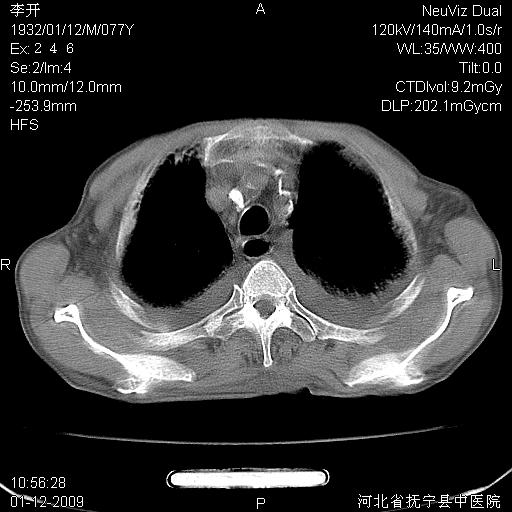

以下是引用黑白光影在2009-1-19 16:49:00的发言:[br]心衰肺水肿;心包、胸腔积液;冠脉钙化;肺部感染。